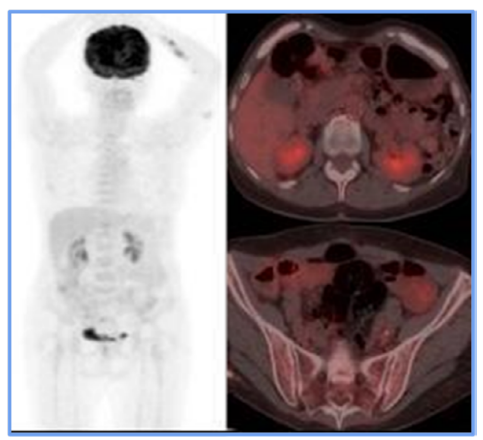

As a result, the treating hematologist recommended a second-line chemotherapy regimen (RICE) for 3 cycles. At the end of these sessions, a follow-up PET scan revealed the resolution of adenopathy in the obturator chain (Figure 3), demonstrating a complete metabolic response. Based on these findings, the patient was declared in remission. Given the favorable evolution, maintenance immunotherapy was initiated with a standard-dose Rituximab regimen for low-grade lymphoma, administered every 2 months for 2 years. As for the writing of this report, the patient has successfully completed 9 cycles and remains in remission.

Figure 2

PET CT before ICE regimen. Only the right internal iliac chain adenopathy was evident (green arrow), which showed FDG uptake, exceeding hepatic uptake about score 4 of the Deauville criteria, suggesting a partial metabolic response to the medical treatment instituted.

For staging, PET-CT (F18-FDG) is a crucial tool. Initially, it allowed for documentation of both nodal and extranodal involvement, establishing tumor viability and aiding in follow-up and evaluation of treatment response. The Deauville 5-point visual scale [7] was used to assess treatment response. In this case, the PET-CT documented persistent disease (Deauville 4), which influenced treatment decisions and led to escalation of the medical management. A subsequent PET-CT (F18-FDG) performed after rescue therapy demonstrated a complete metabolic response at the end of treatment [8].

In the case presented here, the patient showed a favorable response to chemotherapy, achieving complete remission and surviving for two years to date. Lymph node and extranodal involvement, along with immunohistochemical findings, enabled the diagnosis and timely treatment initiation (Figure 1). The partial metabolic response observed in the post-treatment PET (Figure 2) led to the decision to escalate the treatment to second-line RICE chemotherapy. Eventually, a new PET-CT (F18-FDG) post-treatment (Figure 3) confirmed a complete metabolic response.